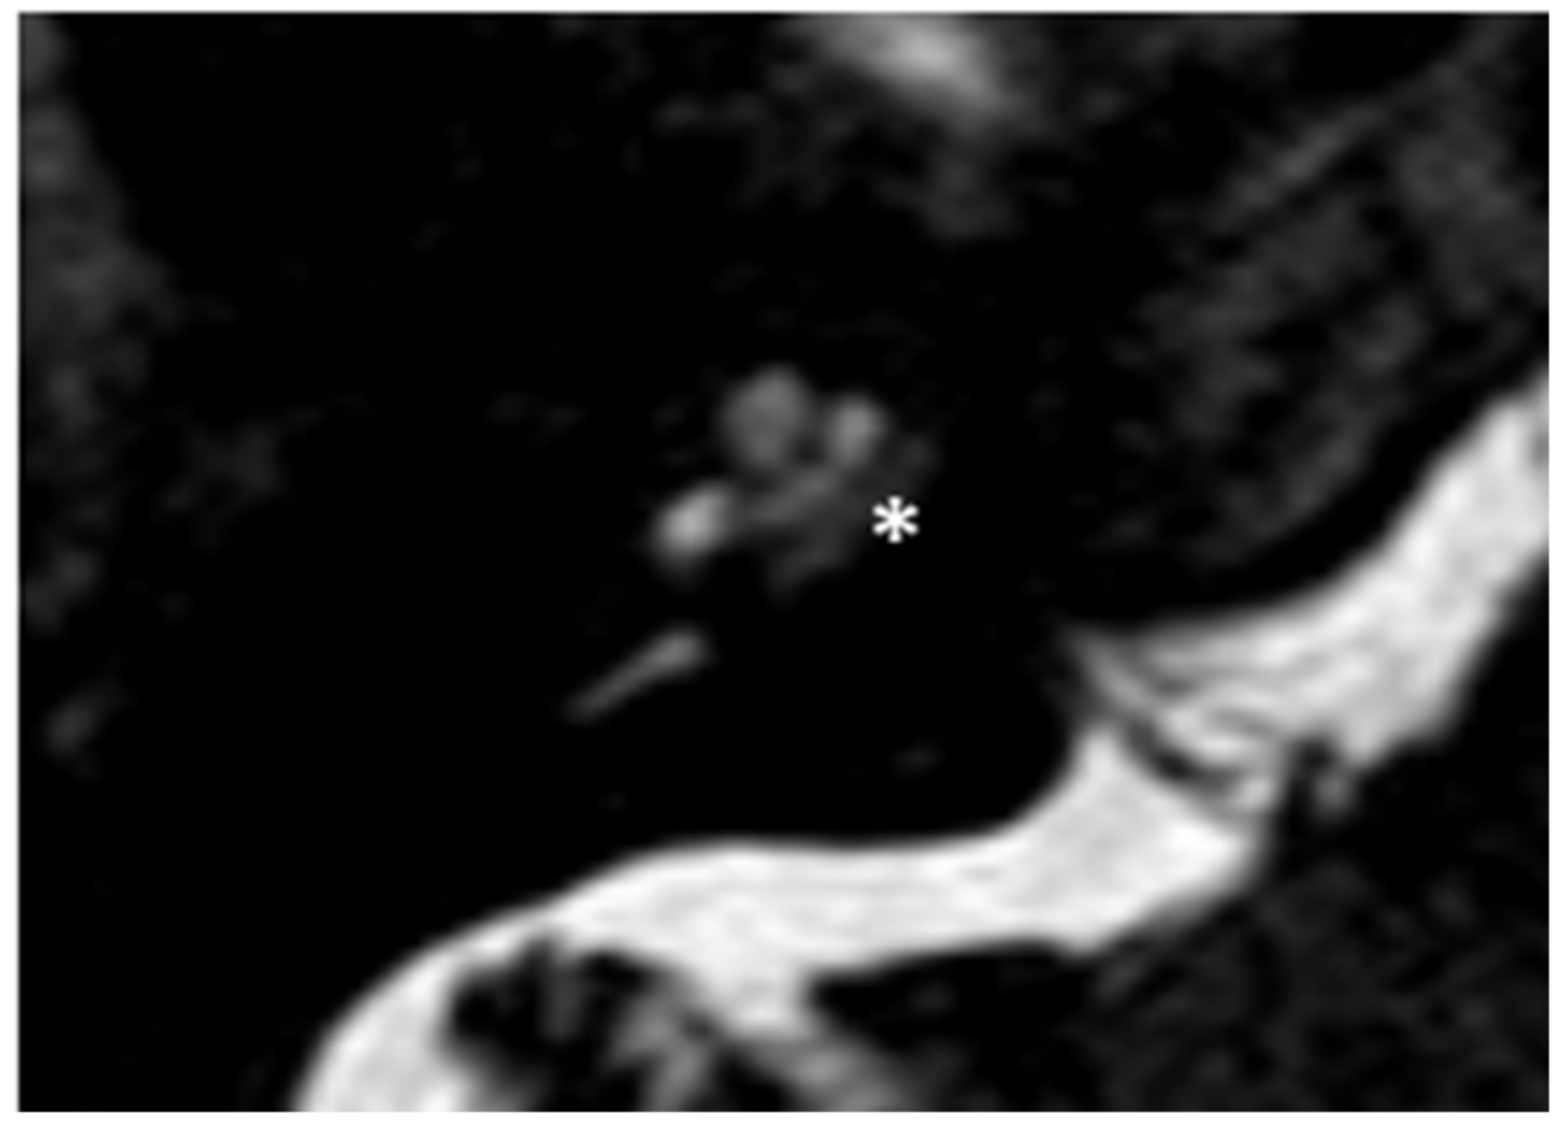

Figure 2.

MR image of patient #1 with osteogenesis Imperfecta. MR cisternography showing the fluid-signal in the newly formed cavity (white asterisk).

Within a few years, both ears showed a worsening of bone threshold to SNHL bilaterally. In 2017 (27 years since diagnosis) she developed profound SNHL with left-sided anacusis and underwent cochlear implantation in the left ear. CT and MR images showed a large cavity around the basal turn of the cochlea and massive osteorarefaction around the cochlea (‘double ring’ sign). The cavity appeared to contain cerebrospinal fluid but did not communicate with the cochlear lumen (Figure 1 and Figure 2).